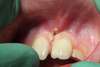

Une section franche, un petit dépôt blanc autour (zone de la gencive suivant la volatilisation des tissus), et le caillot formé automatiquement (en noir).

L'enfant repart avec comme seul conseil de ne pas brosser cette zône surtout quant elle deviendra blanchâtre (2 à 4 jours après et pendant une petite semaine).

C'est un caillot de fibrine pur (et non de sang), il permet une réparation tissulaire spéctaculaire et très rapide.